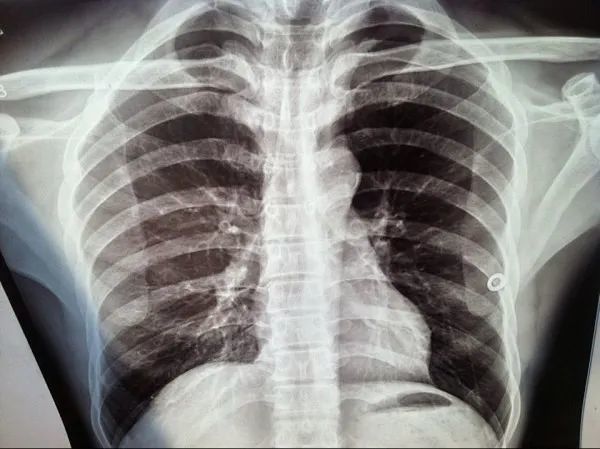

患者胸骨柄处痛特别是按压痛较明显叩击不痛请看胸片有什么问题

胸锁关节,胸骨柄区病变影像诊断专题讨论 [精华]